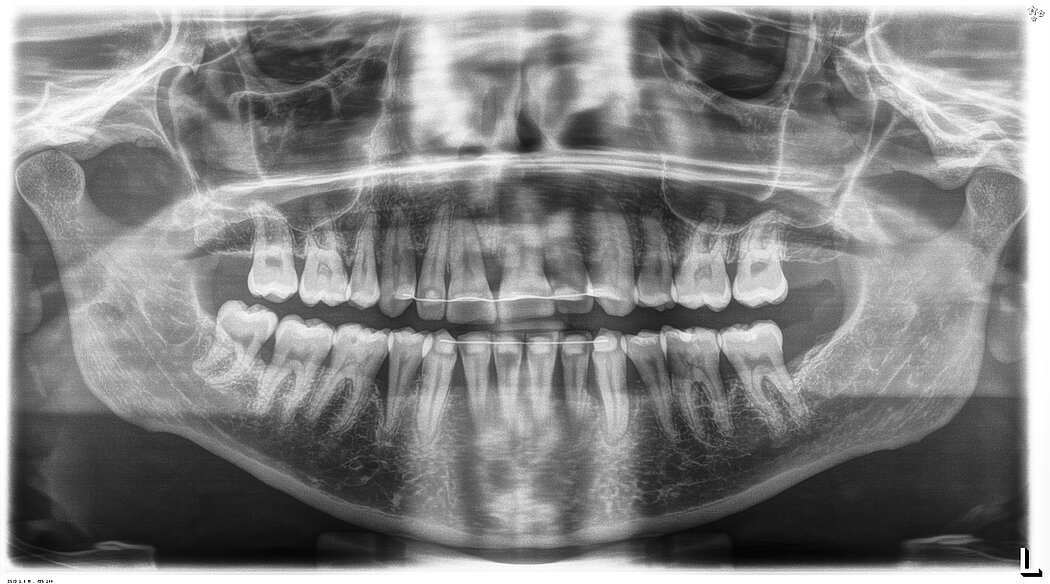

X-ray

Periodontal status before treatment with Pocket-X® Gel